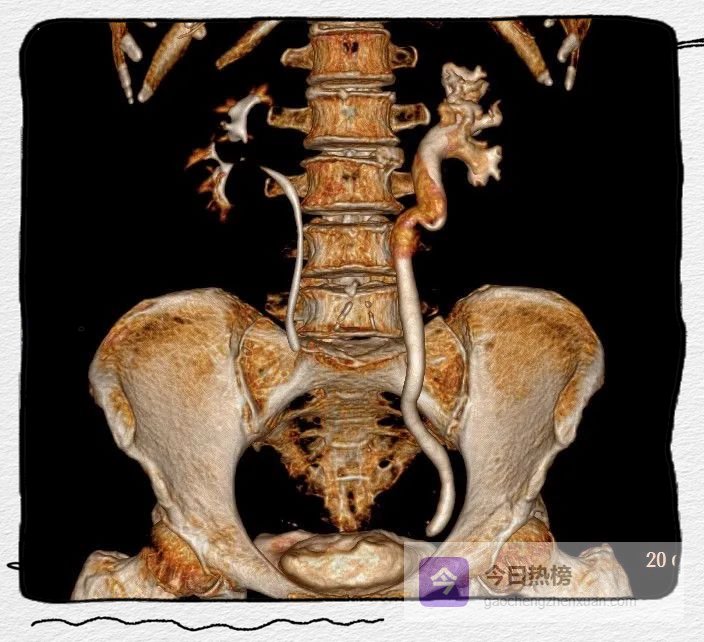

图4A

图4C

图4A-C

左侧肾盂及输尿管上段呈“双环及双腔样”改变,考虑夹层形成;三维重建可清楚的观察到撕裂肾盂及输尿管的真假腔并显示撕裂范围。